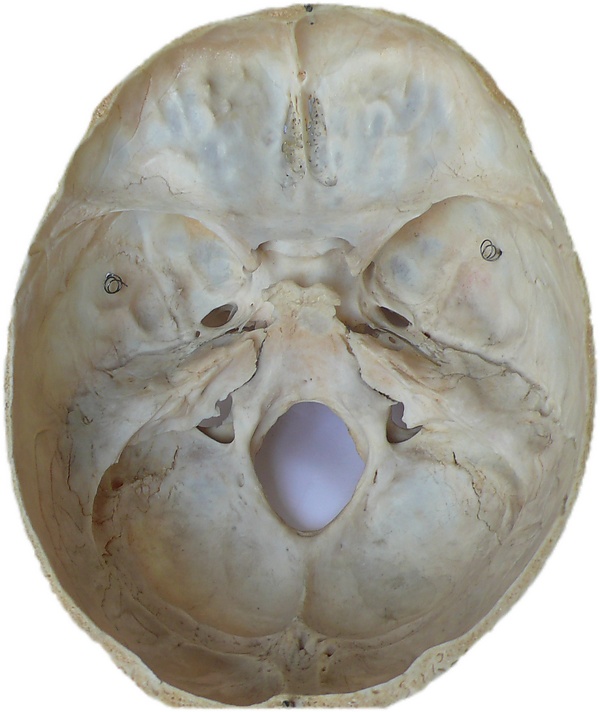

Ушиб головного мозга (лат. contusio cerebri) — черепно-мозговая травма, при которой происходит поражение непосредственно тканей головного мозга, всегда сопровождается наличием очага некроза нервной ткани. Наиболее часто очаги повреждения располагаются в области лобных, височных и затылочных долей. Повреждения, развившиеся при травме, могут быть как односторонние, так и двухсторонние[2].